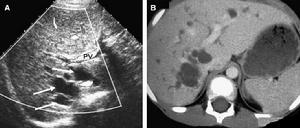

圖1 先天性肝內膽管囊狀擴張症腔常擴張,伴有纖維組織增生;②匯管區的門靜脈小分支仍明顯可見,匯管區之間常有纖維條索相連;③肝小葉結構基本正常。Mereadie指出先天性肝內膽管囊狀擴張症的典型病變常見於匯管區,即僅侵犯肝葉段內的膽管,擴張的膽管及其近端引流的膽管纖維組織浸潤,膽管壁增厚,內含多條擴張的毛細膽管,膽管上皮可呈乳頭瘤樣增生。大體標本可見肝內膽管單個或多個圓形或卵圓形膨大,大小約2~10cm,擴張的膽管走行迂曲,呈“蛇遊動形”,近肝門部膽管因分支多,還可呈“叢狀”或“樹枝狀”,明顯的肝內膽管擴張,切面見有大小不等的囊泡,易於與多囊肝混淆,但腔內瀦留的是膽汁而不是液體,顯微鏡下可見上皮細胞受壓而變得扁平,而多囊肝囊壁則無上皮。擴大的膽管周圍肝實質顏色正常,無萎縮。組織學檢查見擴張膽管的周圍有豐富的神經束,有的呈腺瘤樣增生,肝小葉結構存在。

膽汁病理圖2.CT檢查 Caroli病的檢查特徵為注射造影劑後加強掃描可發現囊狀擴張的中央點狀影,稱為“中央斑點征”,這相當於擴張膽管內有門靜脈小分支生成形成橋狀。CT尚可發現肝門處的膽管相對狹窄,利於術前評估和選擇手術方式。Seth等認為,“中央斑點征”足以提供準確的診斷而不藉助於損傷性或昂貴的檢查。